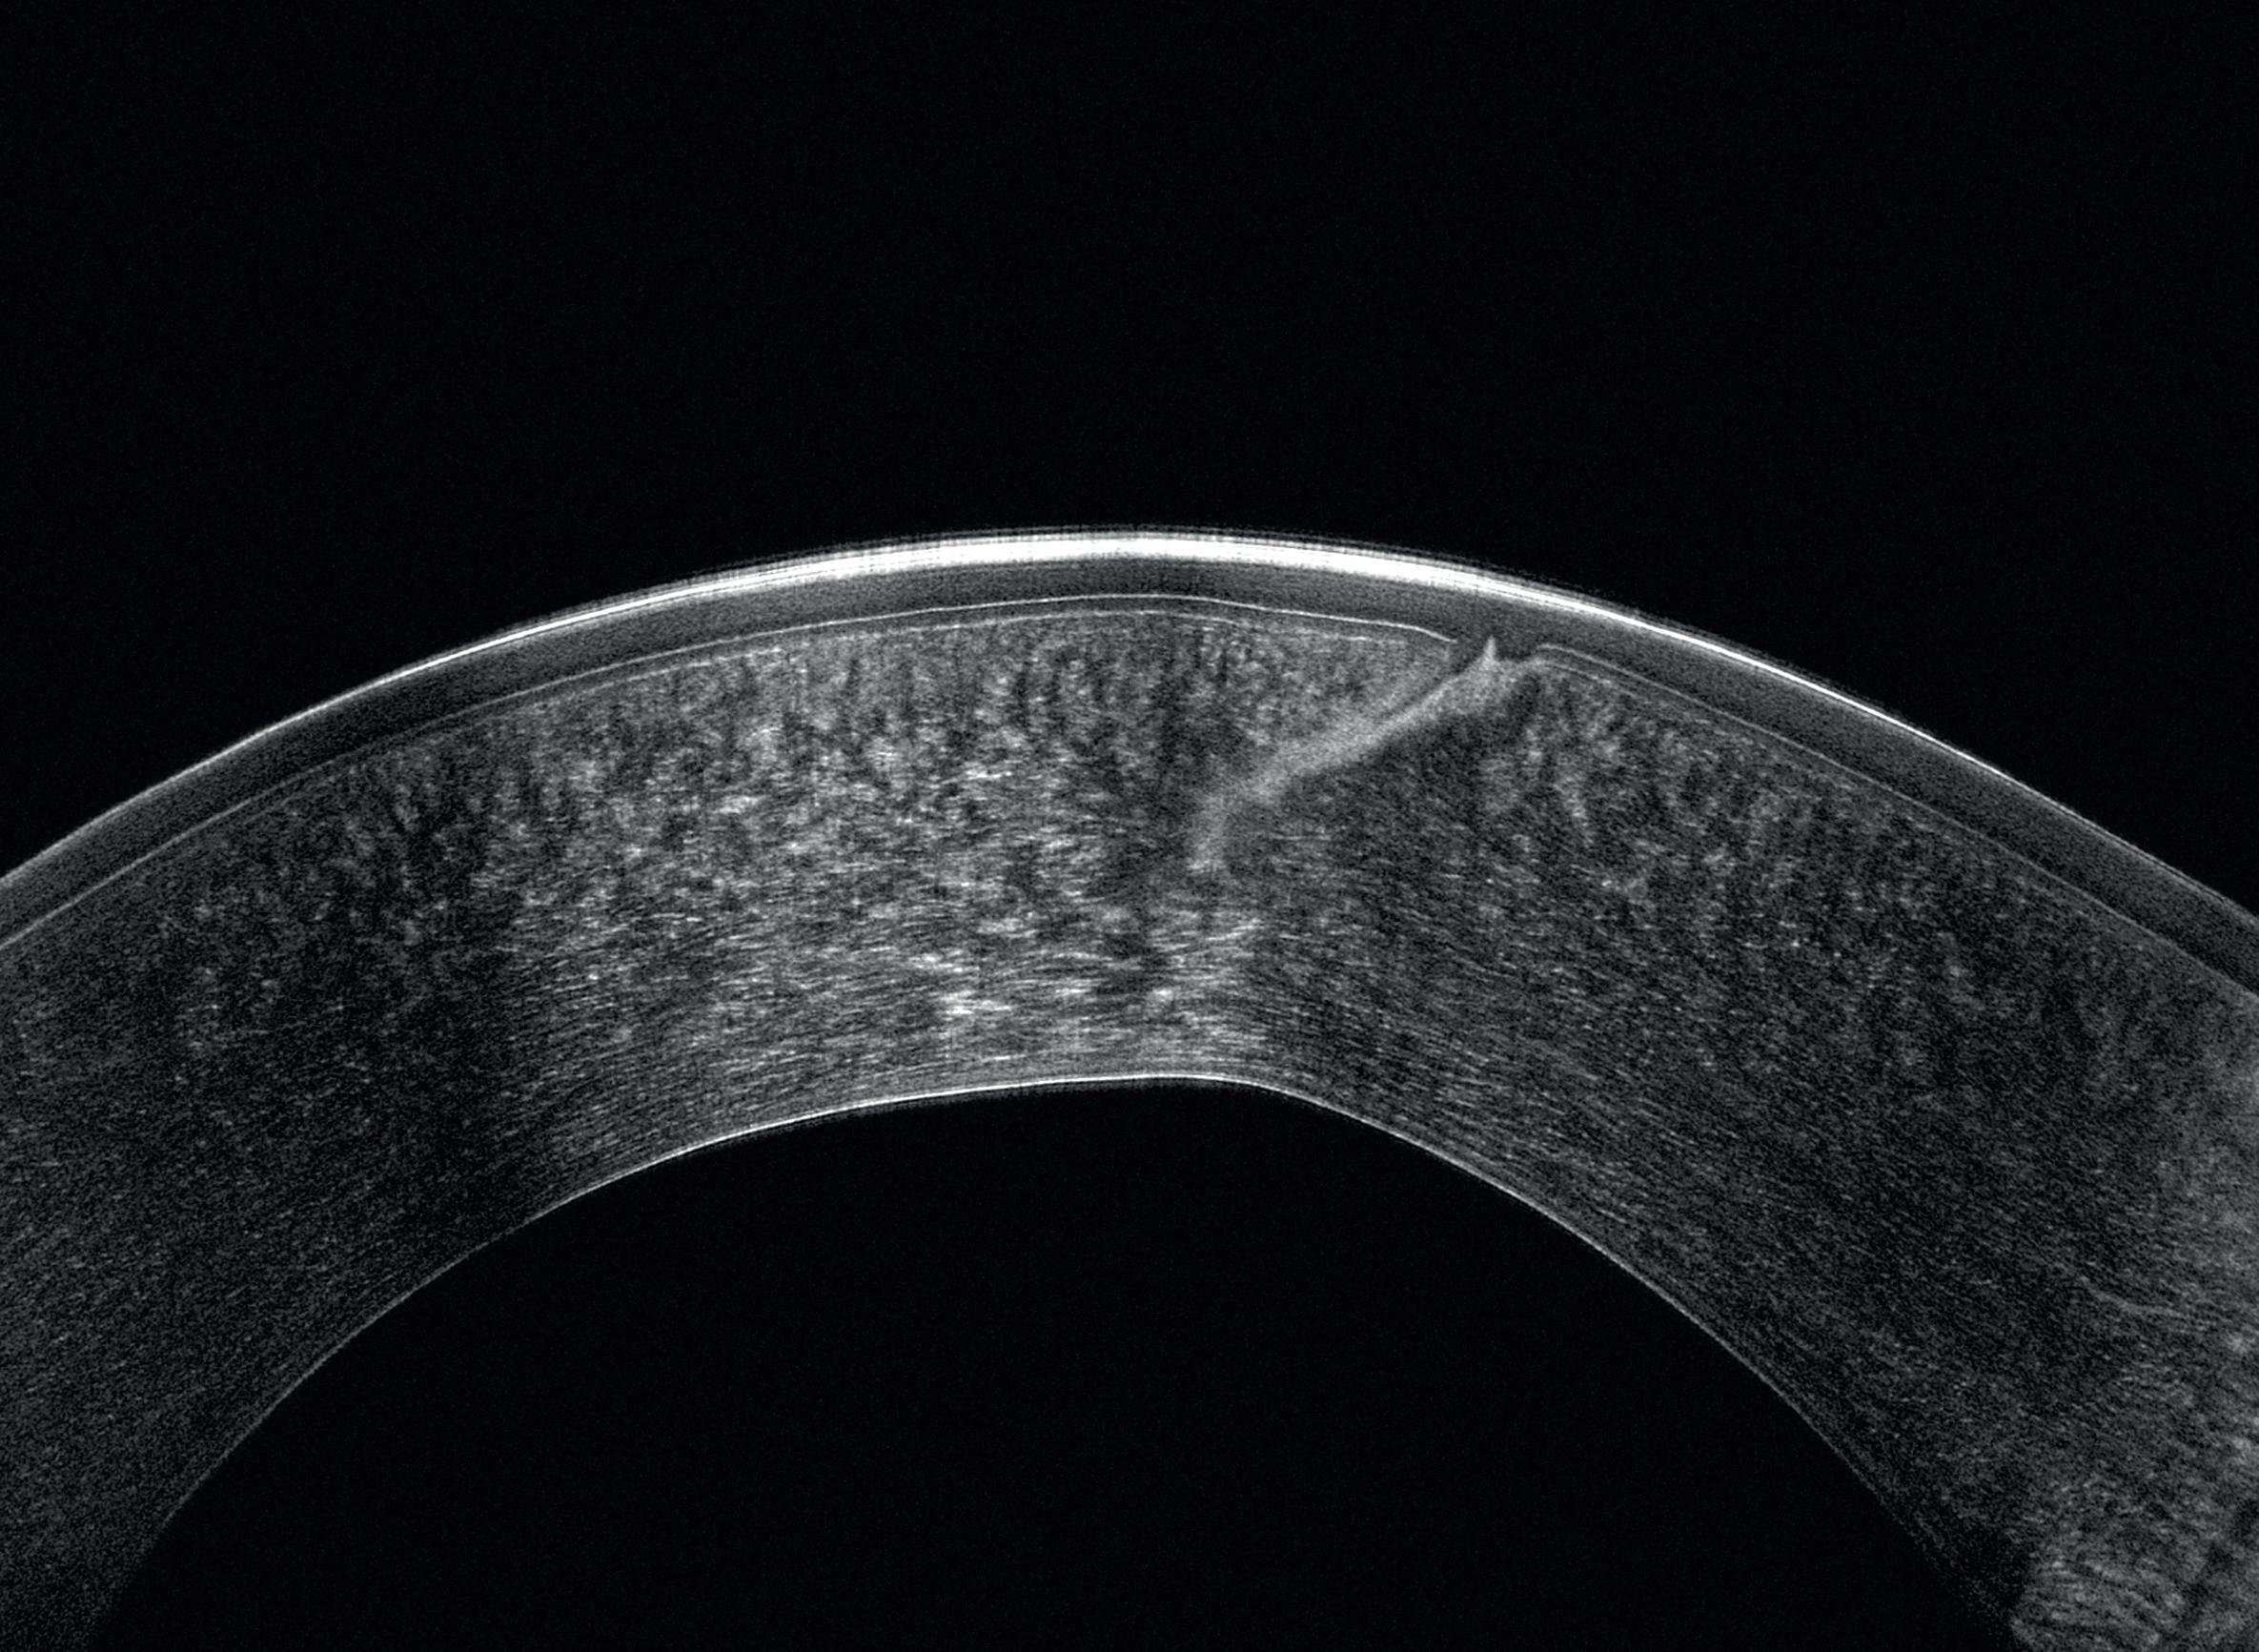

A novel procedure promises to make allogenic intrastromal ring implantation easier and more effective.

The introduction of corneal allogenic intrastromal ring segment or CAIRS by Dr Soosan Jacob in the mid-late 2010s was a welcome addition in treating non-CXL-eligible patients with keratoconus, an important step forward from the classic PMMA intrastromal rings (with far fewer side effects in severity and frequency), and a new alternative to corneal transplantation.

Despite the innovative approach and the ironclad rationale, introducing soft corneal tissue in the stroma is not an easy task, leading experts to strive for a way to make the procedure less challenging. Dr Shady Awwad was the first to propose stiffening the corneal rings through a process of dehydration, an idea that made the insertion procedure a bit easier but lacked efficacy by comparison.

Inserting a CAIRS has a steep learning curve, since the surgeon is dealing with soft tissue. Even using the technique conceived by Dr Awwad has some procedural difficulties, Dr Cosimo Mazzotta observed. Dehydrating a CAIRS can be helpful in terms of insertion, added Dr Marco Zagari, but surgeons end up with a stiff ring that might not have the same efficacy as the non-processed one.

According to both Mazzotta and Zagari, finding common ground between ease and efficacy was the key to improving this procedure, and the best way to achieve this goal was to use riboflavin and UV light.

To find the lowest common denominator, Dr Zagari noted it was necessary to improve Dr Jacob’s idea through Dr Awwad’s mindset. Keeping that in mind, Dr Mazzotta added the decision was to make allogenic intrastromal rings stronger, but not stiffer, using corneal cross-linking.

Processed with a vector-based customised nomogram, the rings obtain a ‘gummy bear’-like solidity, effectively exceeding the dehydrated rings in terms of ease of use. Dr Mazzotta observed this is unheard of in the field of corneal surgery, a completely distinct perspective that generated something brand new and feasible for surgeons globally.

It is a solution that offers high rates of repeatability and opens previously impossible new prospects, Dr Zagari said. Everything is calculated using topographic data from both donor and recipient and precisely cut with a femtosecond laser—based on a specific nomogram designed by the authors and vectorial analysis provided by MS-39 CSO tomography.

Soon it will be possible to calibrate levels of elasticity and elastic recoil with the potential to have a ring that is perfectly tailored to the patient’s needs, he added.

The PMMA-like consistency of cross-linked CAIRS makes the insertion like the non-allogenic intrastromal rings, underlining how the procedure does not require a second point of access. Moreover, the low or absent immunogenicity of cross-linked and decellularised collagen completely reduces the risk of rejection.

Drs Mazotta and Zagari conducted a preclinical study with the Siena Crosslinking Centre and the Veneto Eye Bank Foundation, with its medical director Diego Ponzin. The study has been presented to the Siena Crosslinking Centre ethical committee, before entering the clinical phase, Dr Mazzotta said. For more information, see C Mazzotta, et al., “Crosslinked All-Femtosecond laser-cut Corneal Allogenic Intracorneal Ring Segments (AFXL CAIRS): Pilot Ex-Vivo and In-Vivo Study in Italy,” Preprints, (2024): 2024081945. As of today, the first all femtolaser-cut X-linked (AFXL) CAIRS has already been implanted in patients with keratoconus in Italy, with very promising results and well-responding patients, Dr Zagari concluded. Dr Mazzotta will present a course covering this topic, “What’s New in Early Diagnosis, Pathophysiology, and Prevention Strategies of Keratoconus,” which takes place Monday, 14:00–15:30, 8.1 P.